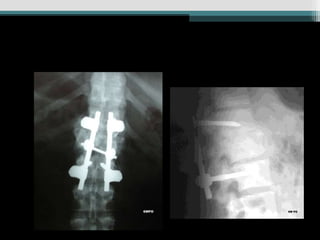

Caso 3 (24anos, queda Fk e)

• 73.

Caso 4 (19anos, auto, Fk e)

• 78.